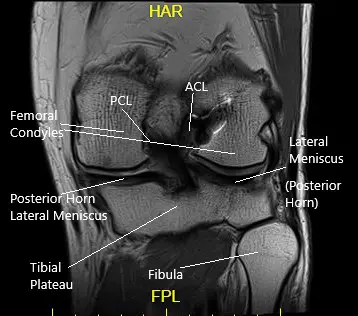

She had an MRI which showed tearing of the medial meniscus at the meniscocapsular junction and posterior horn-body junction. There was tri-compartmental cartilage loss.

Coronal MRI view of the left knee.